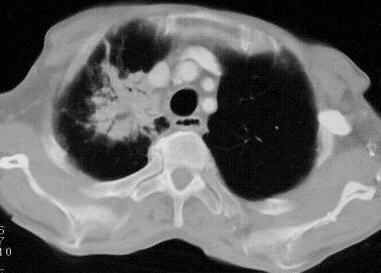

Pleuraergüsse beidseits mit Dystelektasen